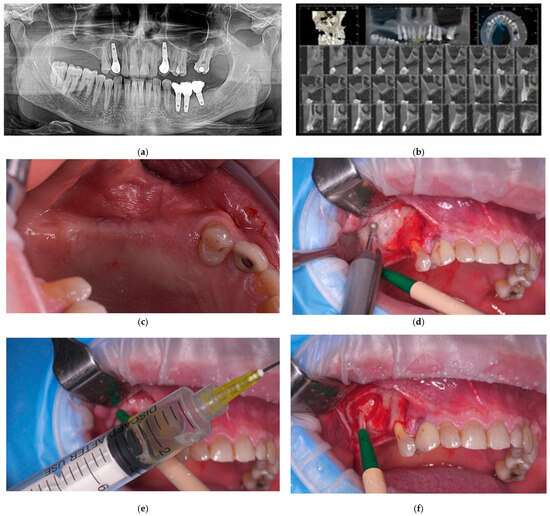

This Special Issue, “Innovations and Challenges in Dental Implantology”, seeks to highlight cutting-edge research and practical insights into key aspects of implantology. Topics of interest include advancements in osseointegration, biomaterials, autologous blood-derived products, and enhanced approaches to guided bone regeneration and bone augmentation. Contributions addressing sinus elevation techniques, peri-implantitis prevention and treatment, soft tissue management, and strategies to mitigate implant failures are highly encouraged. Furthermore, we welcome studies focusing on surgical or non-surgical salvage techniques, providing valuable insights into the management of complications in dental implantology.